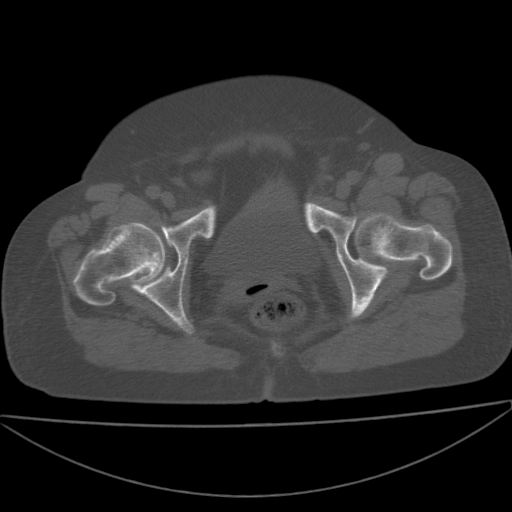

以下是引用余辉在2009-4-23 17:08:00的发言:[br]考虑右髋关节退行性变.股骨颈改变考虑陈旧性骨折可能,股骨头顶部关节面下似有透亮区,股骨头皮质环增厚,考虑有股骨头坏死

以下是引用王显瑞在2009-4-23 16:45:00的发言:[br]考虑股骨颈陈旧性骨折,股骨头缺血型坏死